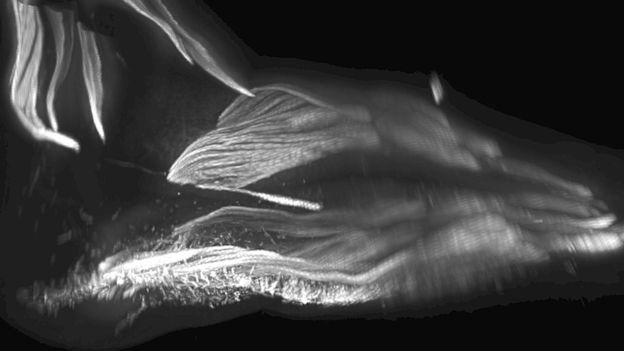

图片版权RUI DIOGO, NATALIA SIOMAVA AND YORICK GOTTONImage caption胎儿脚部肌肉成像

生物学家已经计划对人体其他部位进行更详细的研究,包括对脚部肌肉的研究。

他们发现,子宫中的胎儿脚部也长有额外的肌肉,但随着胎儿的发育随后又消失了。

但人类的近亲猿类和猴子就保留了这些肌肉,因为它会在他们攀援时派上用场。